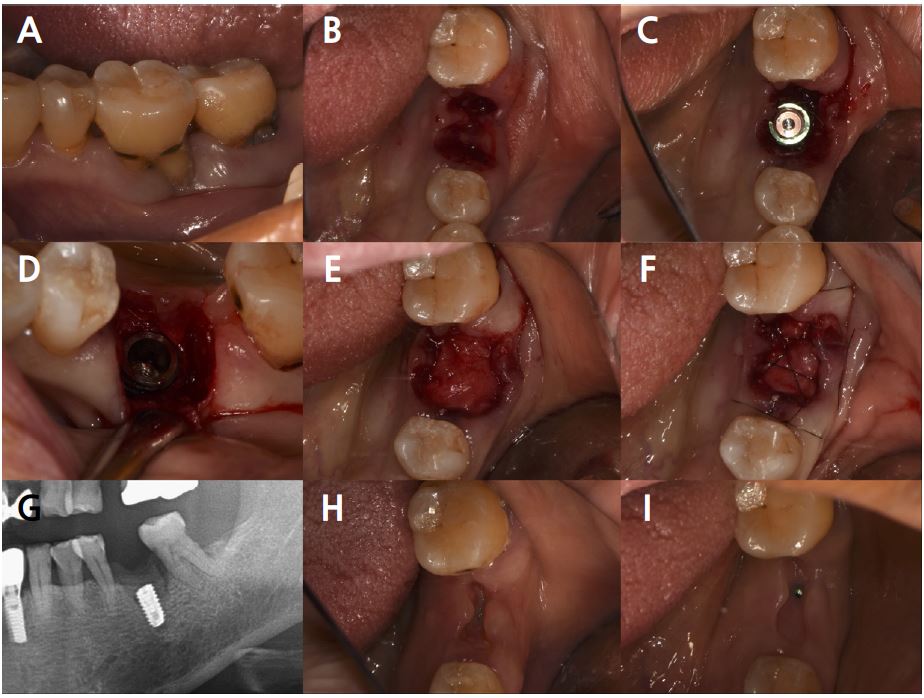

Clinical examination revealed grade 3 mobility with the gingival recession of the distal root of the left mandibular first molar (#36). Radiographic examination confirmed apically involved alveolar bone loss around the mandibular left first molar, however, at a sufficient distance from the mandibular canal (Fig. 1). It was determined that initial stability could be achieved in the apical area, and extraction and iARP were planned. The patient was instructed to rinse with 0.12% chlorhexidine digluconate solution (hexamedine; Bukwang, Seoul, Korea) for 2 min for oral disinfection. The mandibular left first molar was extracted using luxators and extraction forceps under local anesthesia with 2% lidocaine containing 1:80,000 epinephrine (Huons Lidocaine; Huons, Seoul, Korea) (Fig. 2A, 2B). After debridement of granulation tissues and irrigation with sterile normal saline solution, immediate implant placement (TS III 5.0 × 8.5 mm; OSSTEM, Seoul, Korea) was performed (Fig. 2C). The implant was placed 1 mm apical to the lingual socket wall, and the buccal side showed the exposure of two threads of the fixture (Fig. 2D). The implant stability quotient (ISQ) value at 1st surgery was 63. A gap between the implant surface and extraction socket wall and exposed buccal implant thread was filled with deproteinized bovine bone mineral (DBBM) (Bio-Oss®; Geistlich Pharma AG, Wolhusen, Switzerland) and covered with a native bilayer collagen membrane (NBCM) (Bio-Gide®; Geistlich Pharma AG) in a double-layer fashion (Fig. 2E). Subsequently, the hidden X suture and horizontal mattress suture (6-0 Ethilon; Ethicon, Cincinnati, OH, USA) were placed over the NBCM without the intention of primary wound closure (Fig 2F, 2G). Fourteen days after surgery, the patient returned for suture removal and postoperative examination. Healing of the depressed soft tissue above the extraction socket was observed, and a delayed healing pattern of the soft tissue with exposure of the cover screw was observed even after 4 weeks (Fig. 2H, 2I).

Fig. 2.

Case 1: Clinical photographs of the immediate implant placement with alveolar ridge preservation. (A) Gingival recession of the distal root of the left mandibular first molar, (B) Buccal gingival depression observed after tooth extraction, (C) Immediate implant placement in the left mandibular first molar, (D) Two threads of the fixture are exposed on the buccal side, (E) Deproteinized bovine bone mineral was placed in the extraction socket and covered with a native bilayer collagen membrane, (F) Hidden X and horizontal mattress sutures are placed, (G) Panoramic radiograph obtained after implant placement, (H) Depressed gingival healing was observed at stitch out (2 weeks), (I) Cover screw exposure with depressed gingival healing was observed during a recall check (4 weeks).